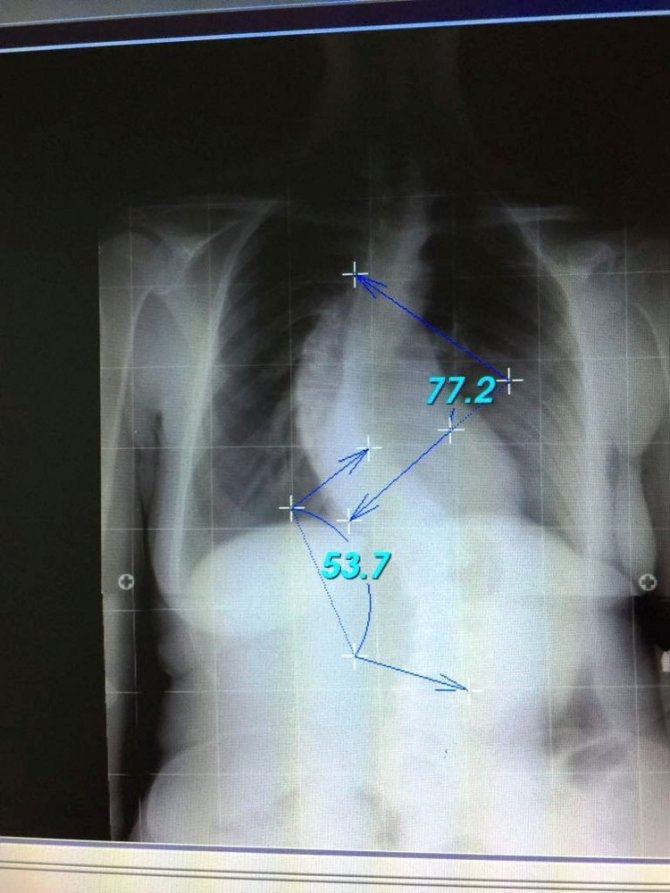

Skolyozda cerrahi tedavi kimlere gerekli

Genelde 45-50 derecenin üzerinde olan eğriliklerin ergenliğin bitip büyüme tamamlansa bile ilerlemeye devam ettiğini söyleyen Önder, "İlerleme sırtta ve belde estetik olarak kötü bir görüntü oluşturduğu gibi akciğer fonksiyonunu da bozabilir. Bu durumda skolyoz cerrahisi yapan çoğu doktor skolyoz eğriliğini azaltmak ya da artmasını engellemek için cerrahi tedaviyi tercih eder. Büyümesi devam eden bir çocukta 40-50 derece arasında skolyoz eğriliği varsa bir çok faktör değerlendirildikten sonra ameliyata karar verilmelidir. Omurganın normalden fazla öne eğilmesine kifoz (kamburluk) diyoruz. Sıklıkla 9-12 yaşlarındaki çocuklarda hızlı büyüme devresinde öne doğru eğilmeleri sonucu omurga kemiklerinin gelişimi bozulup kamalaşmalar oluşmaktadır. Onun için ilkokul öğretmenlerine beden eğitim öğretmenlerine ve başta ailelere çocukların normal pozisyonda durmalarını sağlayacak bilgiler verilmektedir. İleri derecede olan kamburluklar kişinin fonksiyonunu bozmakta. Erkek çocukları askerlik yapamamaktadır. Onun için postür (duruş) bozukluluğu olan çocukların erkenden doktora götürmeleri sadece egzersiz veya özel cihazlarla kamburluk önlenebilmektedir. Geç kalan durumlarda kamburluk derecesi artanlarda tedavi cerrahidir. Bununda hastaya, aileye ve devlete faturası büyük olmaktadır" şeklinde konuştu.